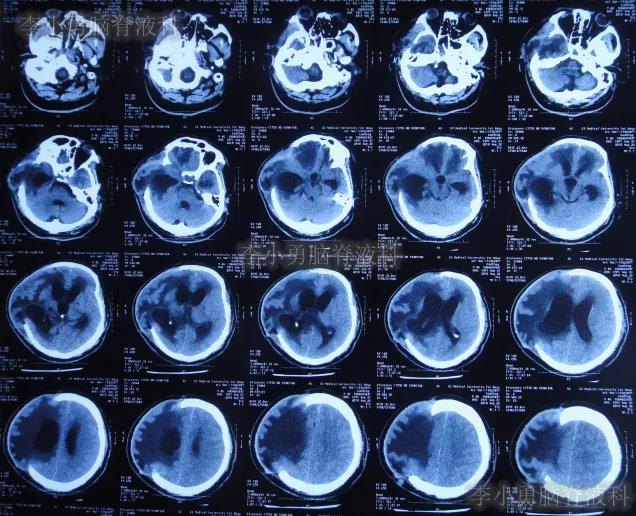

颅骨修补术后7天即2019年4月9日,查头颅CT头颅示颅骨修补术后,仍脑积水(图-4)。

图-4:2019年4月9日头颅CT

颅骨修补术后35天即2019年5月7日(第4家医院治疗227天即脑室腹壁外引流术后211天)),查头颅CT仍脑室扩张(图-5),且引流出的脑脊液有絮状物。

图-5:2019年5月7日头颅CT

第4家医院治疗257天(8个半月),治疗期间患者曾发作癫痫数次,给予药物控制,引流管也曾更换,虽无发热但意识改善不明显,2019年6月6日查头颅CT示脑室仍大(图-6)。

图-6:2019年6月6日头颅CT

第4家医院治疗312天(10个月),意识仍无明显改善,查头颅CT(图-7)后仍脑室扩张,患者出院转回当地的新疆鄯善县某医院。

图-7:2019年7月31日头颅CT